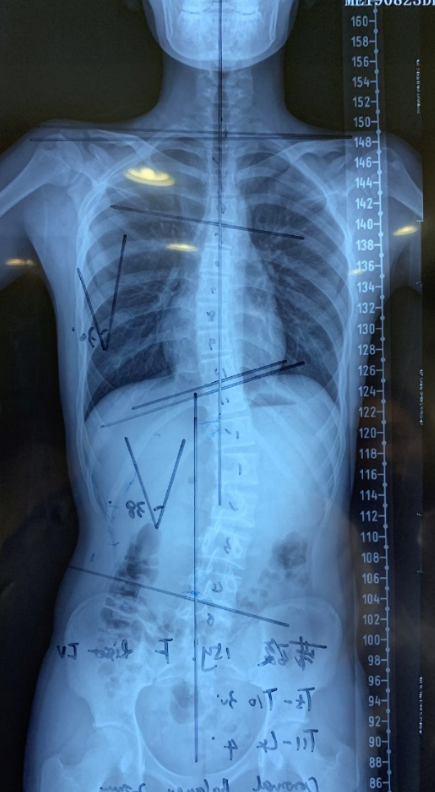

初诊:男14岁,于18年8月发现脊柱侧弯并拍摄脊柱全长X光片,影像检查显示Cobb角胸弯24°,腰弯30°,risser征4级,剃刀背,腰椎锥体旋转。部分医生建议手术治疗,家长想尝试保守治疗方式,遂于我院3D打印中心就诊。

因异地和疫情影响,半年未能复诊,于2020年7月21日佩戴10个月后至医院复查,脱矫形器20小时后拍片显示cobb角胸弯14°、腰弯18.5°,剃刀背改善,矫正疗效明显。